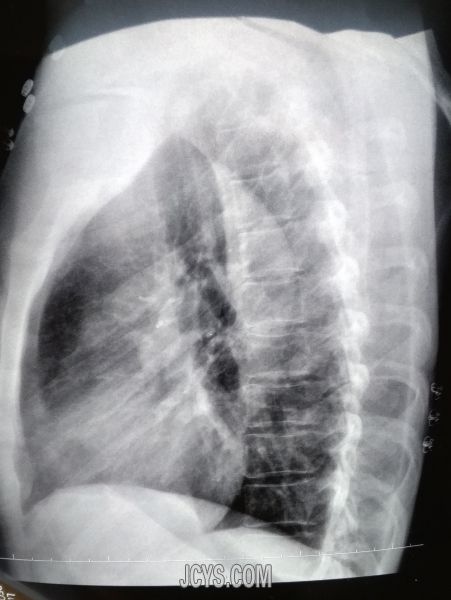

• 一例肺心病患者的治疗 agree

• 凡尘 2017-2-17

• 昨天,刚结束了对一名肺心病患者的治疗。从医十六年了。遇到过不少这样的患者。有经过治疗,好转的。有效果欠佳,转院的。看着病人喘息,胸闷气短,动则更甚的情况,痛苦的表情。每次都不由自主的起急,弄的自 ...  阅读全文>